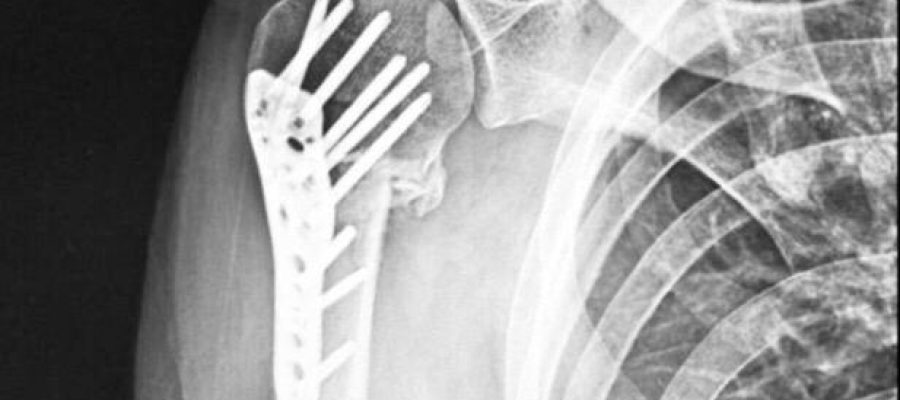

A Equipe da Movimente Reabilitação está preparada para atender os pacientes com disfunções ortopédicas, como: osteoartrose, lesões por traumas articulares e ou musculares, fraturas, pós-cirurgias, lesões tendíneas e ou ligamentares. A Equipe tem sempre o comprometimento com o retorno mais rápido possível do paciente às suas atividades de vida diária e laborativa.